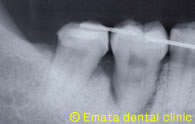

右下の奥歯が経過が悪く、腫れたりするので抜歯と診断しました。反対側に不必要な親知らずがありますので、移植を行いました。

赤枠部分の拡大

移植後3年のレントゲン写真です。良好な状態を維持しています。